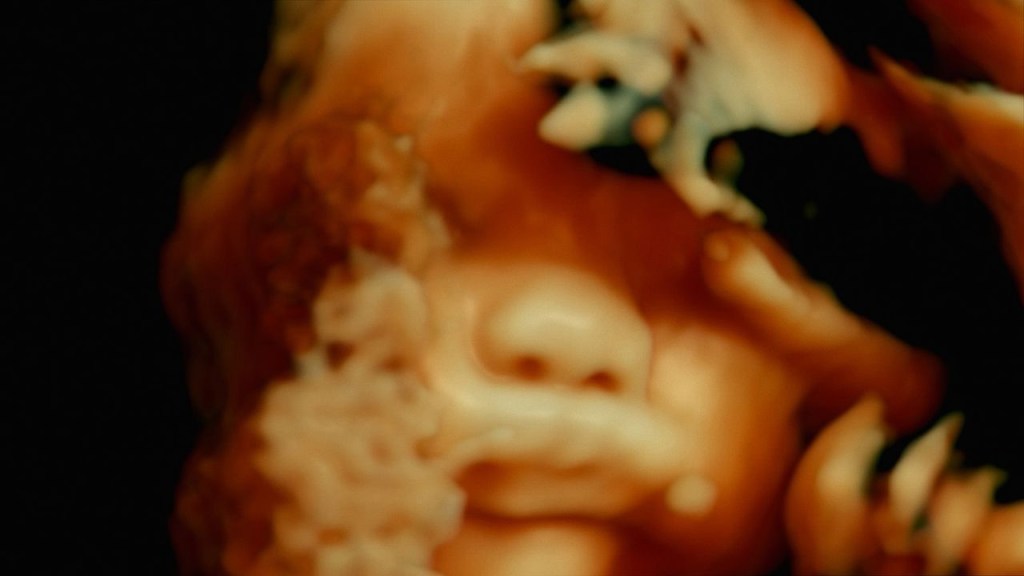

Le cinéma de Paravel et Castaing Taylor est définitivement un sommet absolu en terme d’images documentaires tout comme en terme d’images cinématographiques, c’est une prouesse, et en plongeant dans la chair, mêlant images médicales et hospitalières croisant les lieux, couloirs, veines, organes, machineries, services, fluides et psychés, De Humani Corporis Fabrica va bien plus loin que le corps et la société, l’humain et la médecine, la vie et la mort.

Ici, vous êtes invités à un voyage où le corps se révèle au-delà de nos perceptions habituelles et devient ôde cosmique, territoire hallucinatoire pour percevoir le vivant et ses structures microscopiques, à échelle de cellules, magma troublant.

Sous la peau se cache un mystère de l’univers la vie et ses formes, la réflexion caresse un absolu, un début et une fin, un foisonnement et son infini.

Oubliez l’espace, le grand voyage vers l’inconnu se trouve sous notre épiderme, dans nos chairs, dans l’organe, le plasma et ses inconnus.

De Humani Corporis Fabrica dépasse le cinéma, atteint un niveau artistique unique en son genre, fait de l’anatomie un dédale dans lequel réside les mystères de l’univers.